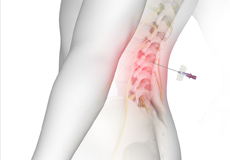

Epidural Spinal Injection

Epidural spinal injection is a non-surgical treatment option utilized for relieving back pain. Spine degenerative conditions such as herniated disc, spinal stenosis and many others may induce back pain due to the compression of the associated spinal nerves. This pain or numbness may extend to the other parts of the body such as hips, buttocks, and legs. Doctors start with non-surgical methods to treat back pain and epidural spinal injection is one of these preferences. In cases where the patient finds no relief from non-surgical methods then finally surgery is recommended.

Epidural Steroid Injections

Epidural steroid injection (ESI) is a minimally invasive approach to treat inflammation of spinal nerves that causes pain in the neck, arms, back and legs. This technique may help relieve back pain in conditions such as spinal stenosis, spondylolysis or herniated discs. In this technique, the steroidal medications are injected into the spinal canal so as to pass down to the inflamed spinal nerve through the epidural space which lies between the covering of the spinal cord and the vertebrae. An ESI contains a corticosteroid medication along with an anesthetic agent which can reduce the inflammation and pain.

Transforaminal Epidural Steroid Injection

The epidural space of the spine is the area between the vertebral bones and the protective dura sac that surrounds the spinal cord and nerves.

Lumbar Epidurals

Lumbar epidurals are injections to treat and relieve low back pain. A lumbar epidural involves injecting a local anesthetic and an anti-inflammatory steroid into the epidural space of the lower spine (lower back) to reduce inflammation causing the pain.